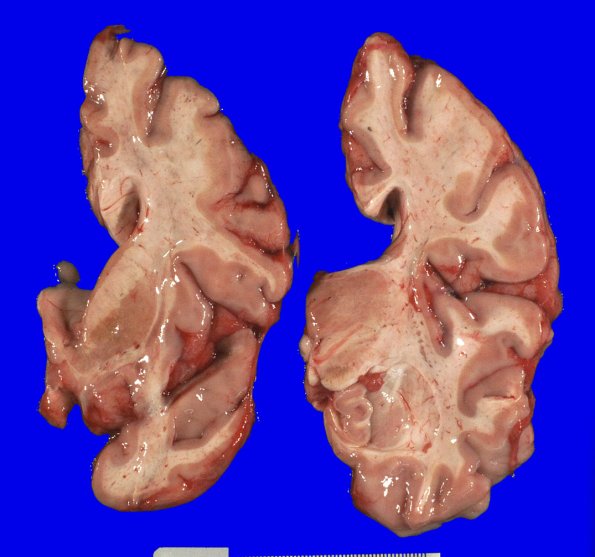

17A2,3 Coronal slicing revealed moderately dilated lateral ventricles and flattened caudate nuclei.